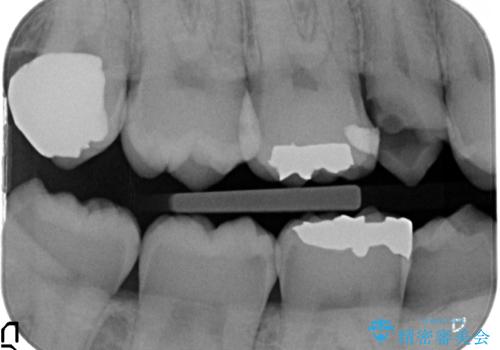

歯茎の中まで虫歯になっており、そのまま完璧に治療をすることは不可能でした。

歯の健康な部分を矯正治療で引っ張り出してから、虫歯治療を行なっています。

- 32万円(右上5:ジルコニアクラウン(スペシャル)10万円、仮歯 1万円、エクストリュージョン:10万円、歯周外科治療:エクストリュージョン費用に含む 根管治療:9万円 ファイバーコア:2万円)費用は治療当時の料金となります